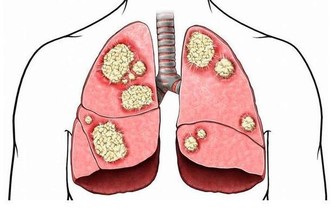

3、肺與脾

脾胃虛最先影響肺。肺像個“宰相”,專門輔佐心臟這個“君主”。肺通過管理體內的氣,協助心臟治理全身。然而,肺氣的盛衰,取決於脾胃的強弱。脾胃虛的人往往會導致肺氣虛,容易患感冒和其他呼吸系統疾病。